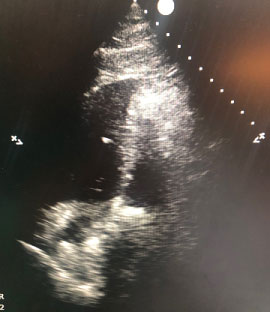

The patient was admitted to the ICU. During admission to the Unit, an echocardiography was performed which showed linear mobile density in the right atrium that displaces atrial septum (Figure 2). In addition, a pulmonary ultrasound was performed showing an image of pulmonary infarction (Figure 3).

Figure 2: Linear mobile density in the right atrium that displaces atrial septum. View Figure 2

Figure 3: Image of pulmonary infarction. View Figure 3